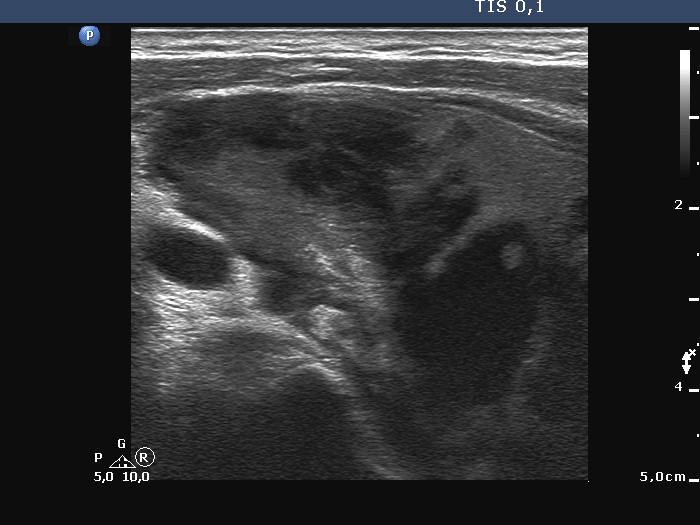

Ultrasonography. The right lobe was extremely enlarged with the dimensions of 50, 50 and 85 mm, depth, width and length, respectively. This lobe was composed of multiple hypoechoic areas within an echonormal background. The left lobe also had a hypoechoic lesion.